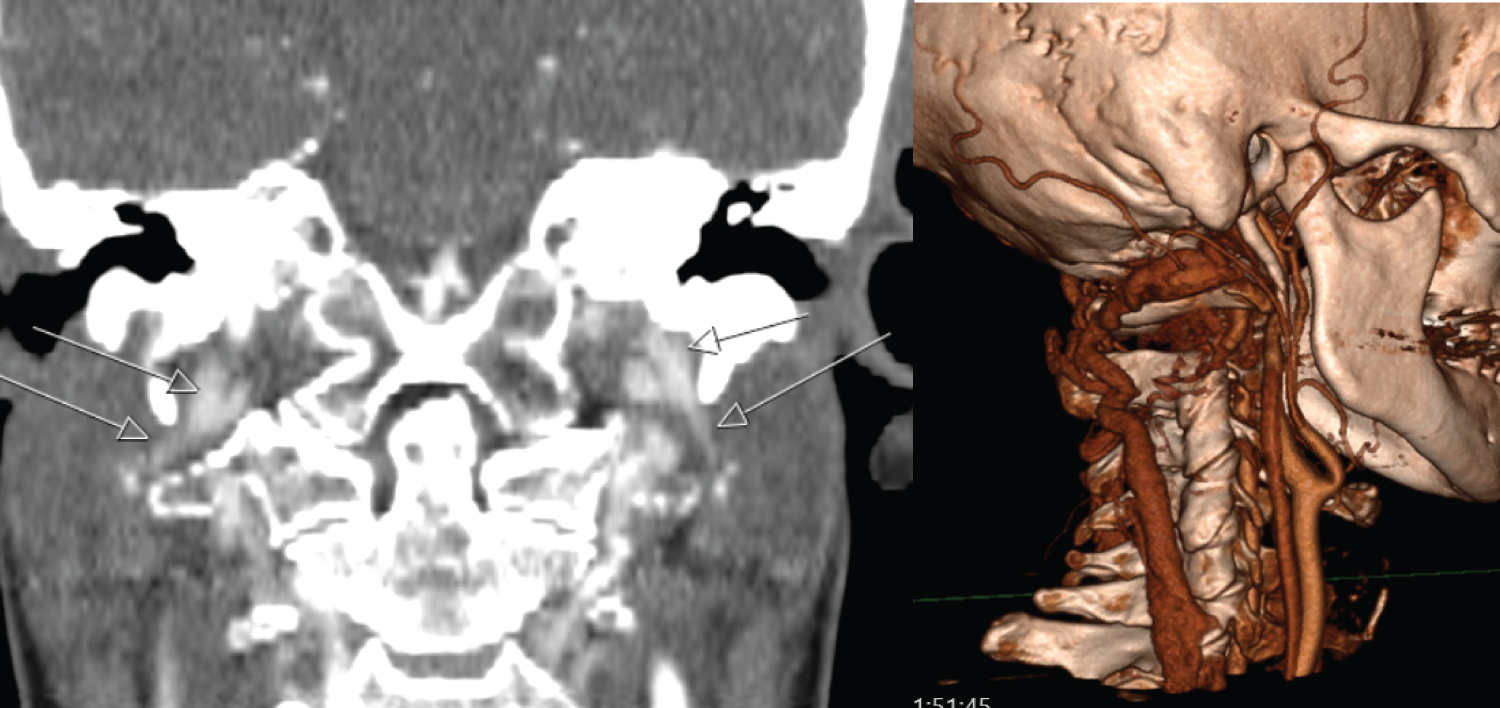

A brain and cervical spine CT angiogram (CTA) was performed as a part of our routine pre-operative planning. Review of this scan in our skull base MDT raised a possibility of bilateral jugular vein obstruction just below the skull base (Figure 2A) with enlarged venous system in the cervical paraspinal muscles (Figure 2B). There was also finding of bilateral elongated styloid processes of 4 cm, with associated bilateral internal jugular vein (IJV) stenosis. The narrowed calibre internal jugular veins continued throughout the neck. The stenosis of the IJVs resulted in a large substantial flow from the sigmoid sinuses into the deep and dilated venous channels in the paraspinal muscle. The concern at this stage was that the paraspinal venous channels were the primary intracranial venous outflow, with potential risks of venous hypertension with brain swelling, and venous infarction in event of any damage during surgical exposure for craniotomy for foramen magnum meningioma. A possible change in surgical approach was considered based on above findings, pending more information. Following discussion with vascular surgery service a doppler ultrasound of neck was performed, which reassuringly demonstrated patency and a reasonable blood flow through both IJVs. There was no evidence of underlying thrombosis (Figure 3). Although this was reassuring, the patient was counselled in detail about small risks of potential venous infarction, surgical access difficulties and incomplete resection.

Figure 2: A) Internal jugular veins narrowing bilaterally at the junction between the styloid process and C1 lateral mass; B) Large, tortuous, engorged anastomotic venous plexus and collaterals to the posterior jugular vein and bilateral vertebral veins. View Figure 2